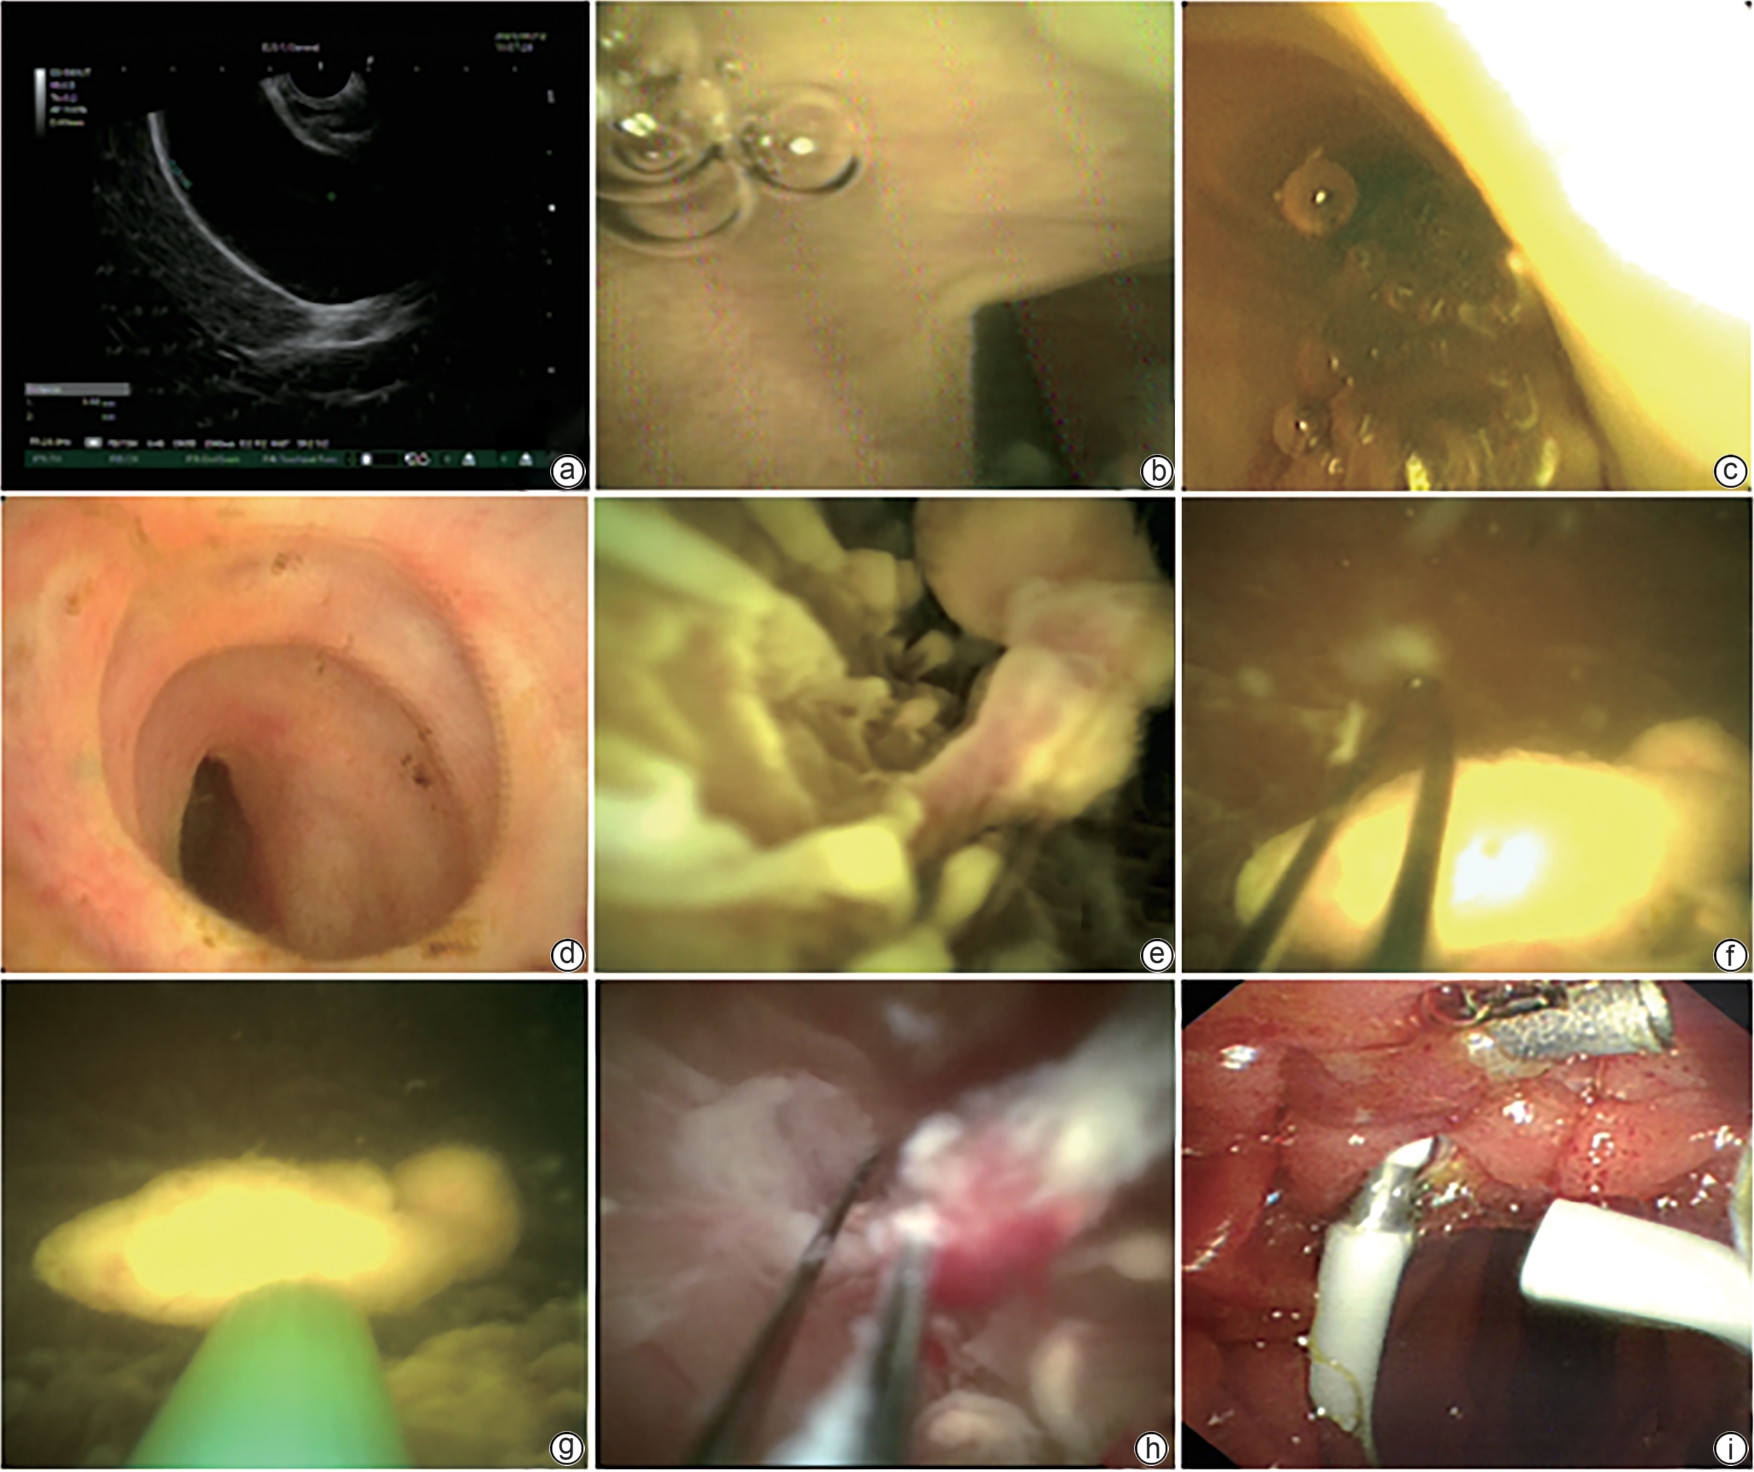

Biliary Disease

Therapeutic effect of different biliary drainage methods after laparoscopic common bile duct exploration in elderly patients with choledocholithiasis: An analysis based on propensity score matching

Kaifang DU, Xichun WANG, Lei WEI, Changzhi ZHAO, Zhongyi FENG, Mingjie CHENG, Hanshuo LI, Guiling LANG

2025, 41(11): 2359-2364. DOI: 10.12449/JCH251124

Abstract:

Objective  To investigate the safety and feasibility of intra-biliary drainage tube placement after laparoscopic common bile duct exploration in elderly patients with choledocholithiasis, and to provide more options for surgical procedures in the clinical management of elderly patients with choledocholithiasis.  Methods  A retrospective analysis was performed for the clinical data of 52 elderly patients with choledocholithiasis who were admitted to Department of Hepatobiliary Surgery, Affiliated Dalian Friendship Hospital of Dalian Medical University, from November 2021 to October 2024. According to the biliary drainage method after surgery, the patients were divided into internal drainage group with 24 patients and T-tube drainage group with 28 patients, and there were 19 patients in each group after propensity score matching. The two groups were compared in terms of perioperative parameters and postoperative complications. The Wilcoxon rank-sum test was used for comparison of continuous data between two groups, and the chi-square test or the Fisher’s exact test was used for comparison of categorical data between two groups.  Results  Compared with the T-tube drainage group, the internal drainage group had a significantly shorter length of postoperative hospital stay and a significantly lower volume of postoperative bile loss (Z=-2.845 and -5.633, both P<0.05), while there were no significant differences between the two groups in time of operation, intraoperative blood loss, and drainage tube indwelling time (all P>0.05). There were no significant differences between the two groups in postoperative bile leak, stone recurrence, biliary stricture, and drainage tube-related complications, and the internal drainage group had a significantly lower total complication rate than the T-tube drainage group [1 (5.3%) vs 7 (36.8%), P<0.05].  Conclusion  For elderly patients with choledocholithiasis, intra-biliary drainage tube placement after laparoscopic common bile duct exploration can shorten the length of postoperative hospital stay, reduce bile loss, and lower the incidence rate of postoperative complications, thereby helping to accelerate postoperative recovery.